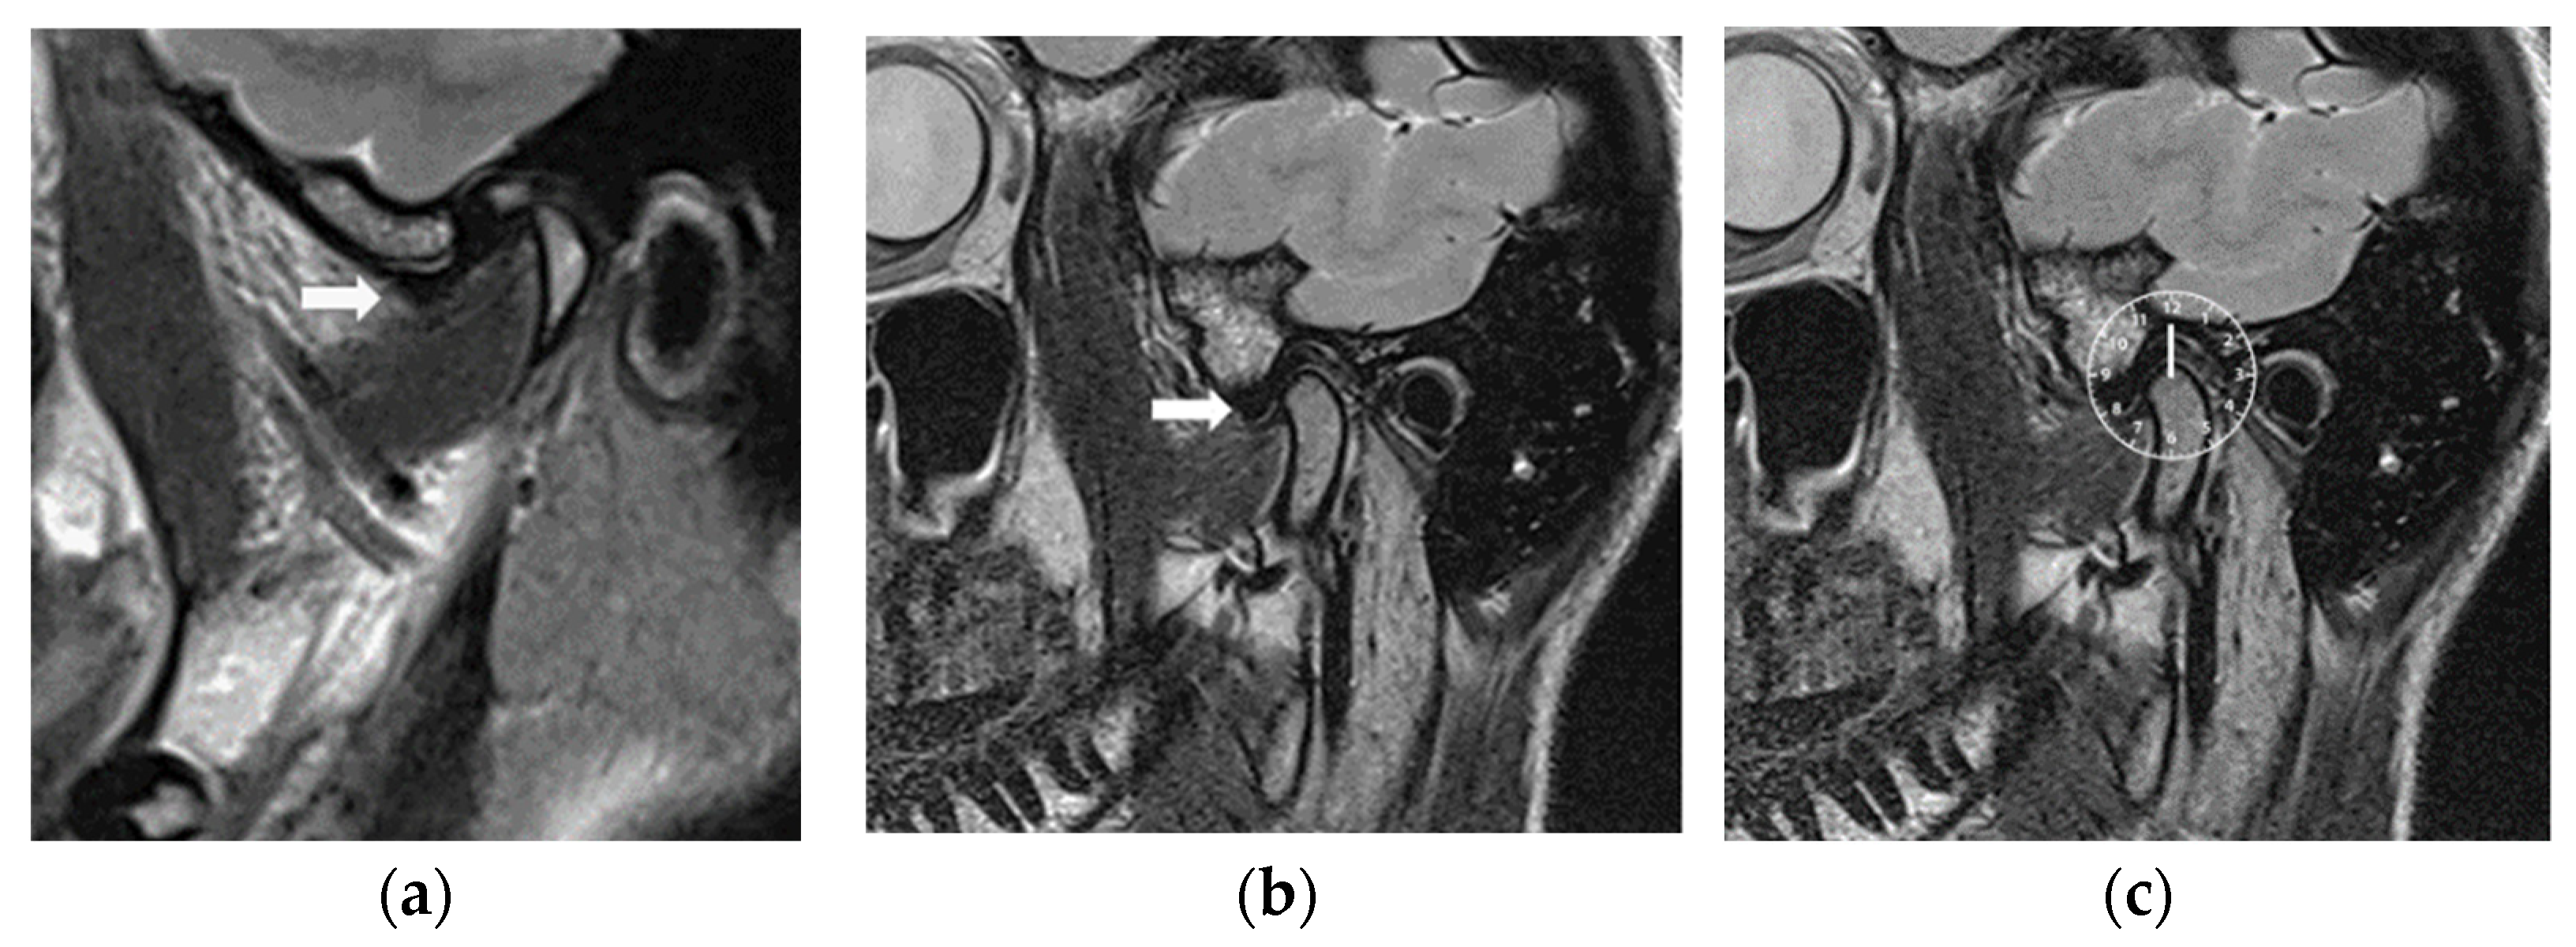

2.2.3. Magnetic Resonance Imaging

| Joint | MRI Slices | Before | After | |||

| Right | 1 | 18 | 10:21 ± 0:30 | 18 | 12:00 ± 0:20 | 0.0002 |

| 2 | 17 | 10:19 ± 0:29 | 18 | 12:01 ± 0:19 | 0.0008 | |

| 3 | 17 | 10:19 ± 0:29 | 17 | 12:03 ± 0:18 | 0.0006 | |

| 4 | 17 | 10:19 ± 0:29 | 17 | 12:03 ± 0:18 | 0.0006 | |

| 5 | 15 | 10:30 ± 0:27 | 16 | 12:03 ± 0:18 | 0.0003 | |

| 6 | 15 | 10:32 ± 0:26 | 16 | 12:03 ± 0:18 | 0.0003 | |

| 7 | 13 | 10:32 ± 0:28 | 15 | 12:04 ± 0:19 | 0.0005 | |

| Left | 1 | 19 | 10:34 ± 0:30 | 19 | 12:03 ± 0:17 | 0.0001 |

| 2 | 18 | 10:31 ± 0:28 | 18 | 12:01 ± 0:16 | 0.0002 | |

| 3 | 18 | 10:33 ± 0:27 | 18 | 12:01 ± 0:16 | 0.0001 | |

| 4 | 17 | 10:31 ± 0:28 | 17 | 12:01 ± 0:16 | 0.0009 | |

| 5 | 15 | 10:36 ± 0:23 | 16 | 12:01 ± 0:17 | 0.0002 | |

| 6 | 15 | 10:28 ± 0:28 | 16 | 12:00 ± 0:18 | 0.0005 | |

| 7 | 13 | 10:25 ± 0:29 | 15 | 11:58 ± 0:23 | 0.0005 | |